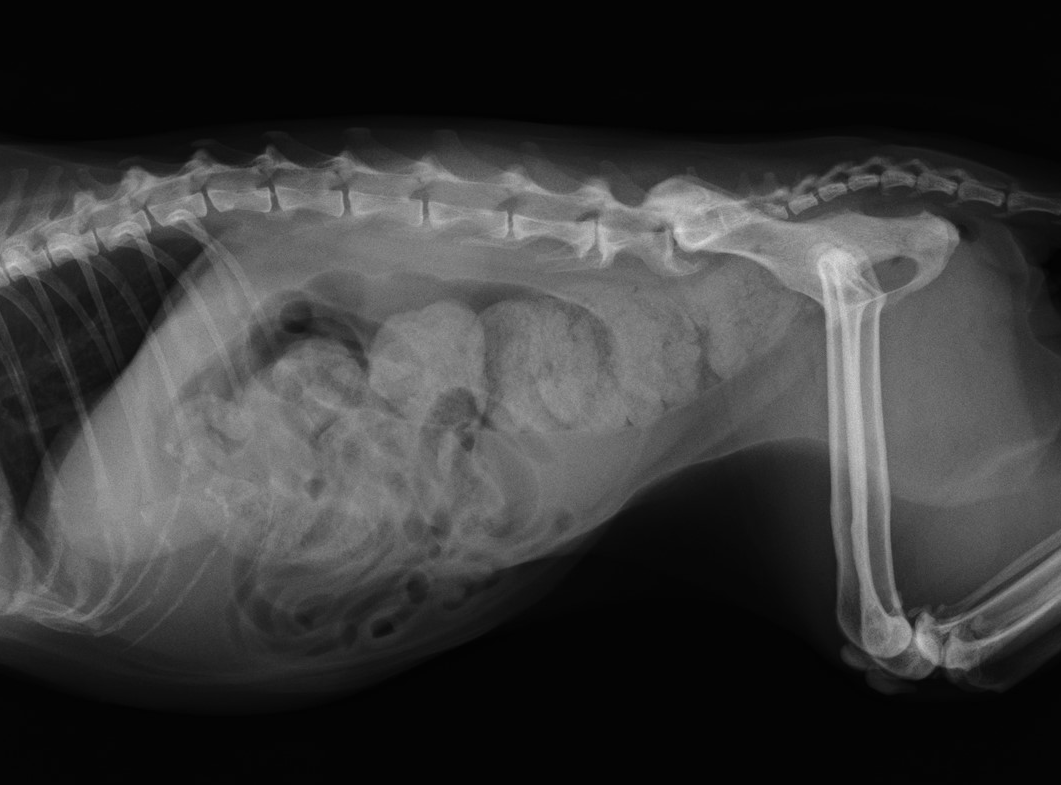

犬 便秘 レントゲン

動物病院の費用(猫の便秘)について 今日猫の便秘で動物病院に行ったら1万368円でした。この金額は妥当ですか。 内訳は 診察料 540円 レントゲン(2枚)43円 浣腸 16円 皮下点滴 1944円 皮下注射 1296円 内服薬(シロップ) 648円 でした。 猫のとらじ、1年半ぶりの便秘で通院中です。 今日撮ったレントゲンは、素人目にもお腹の中がウンチでギュウギュウでした。 今回の便秘の経過は、 10月8日に普通に排便 10月9,10日に便秘 レントゲン検査: 4000~8000円 (犬の大きさにもよる) 『バリウム造影検査』 レントゲンや超音波検査で胃や腸に 何らかの異常が見られる場合には より詳しく状態を見るための造影検査 が行われることもあります バリウム造影検査では 胃や腸管の

犬 便秘 レントゲンのギャラリー